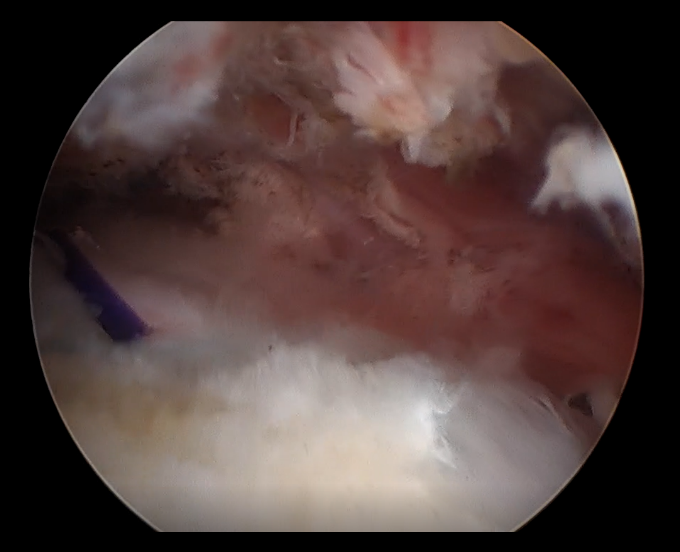

حقق قسم جراحة العظام في مستشفى المانع فرع الخبر إنجازًا طبيًا لافتًا، بقيادة الدكتور محمد المجتبى بعد أن تمكن مريض يبلغ من العمر 61 عامًا من استعادة كامل مدى الحركة في كتفه خلال أربعة أسابيع فقط من خضوعه لعملية إصلاح الأوتار بالمنظار باستخدام رقعة الكولاجين التعويضية، وهي تقنية طبية حديثة تُستخدم لتعزيز التئام الأوتار وتسريع عملية التعافي.